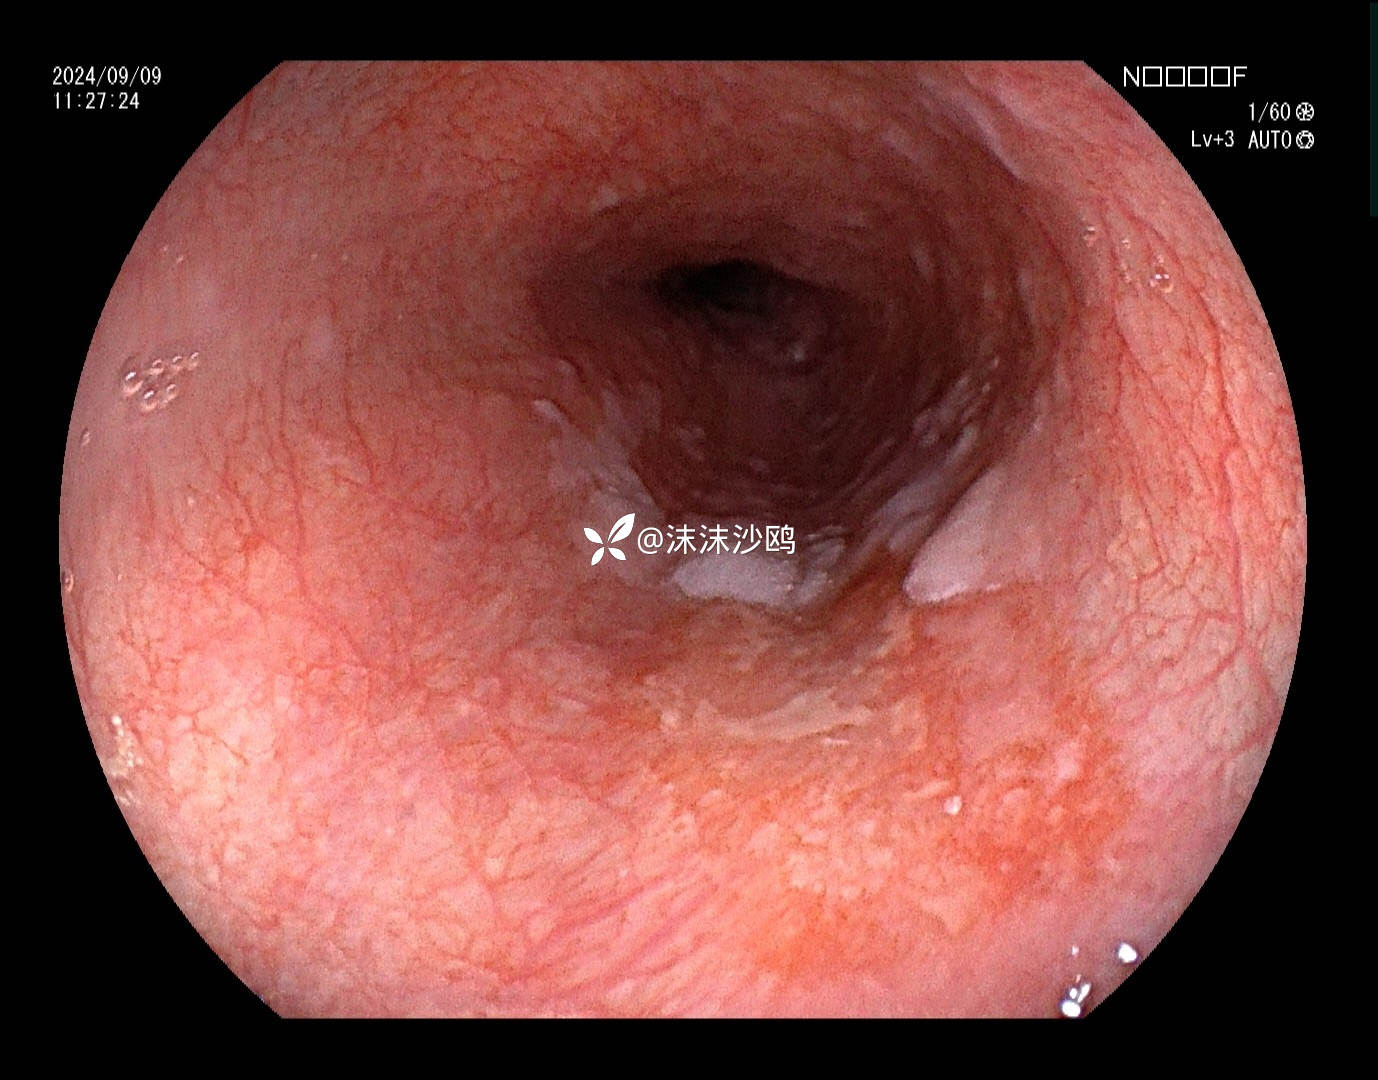

老年男性,腹胀不适门诊行普通胃镜检查。距门齿30cm见片状粘膜粗糙发红,呈0-II b型病灶。

距门齿30cm见片状粘膜粗糙发红,大小约2cm,形态0-II b型

LCI